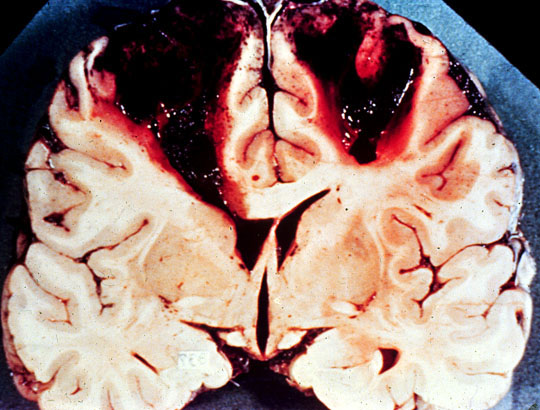

Brain, thrombosis, superior sagittal sinus, gross

Bilateral hemorrhagic infarcts in draining area of superior sagittal sinus.